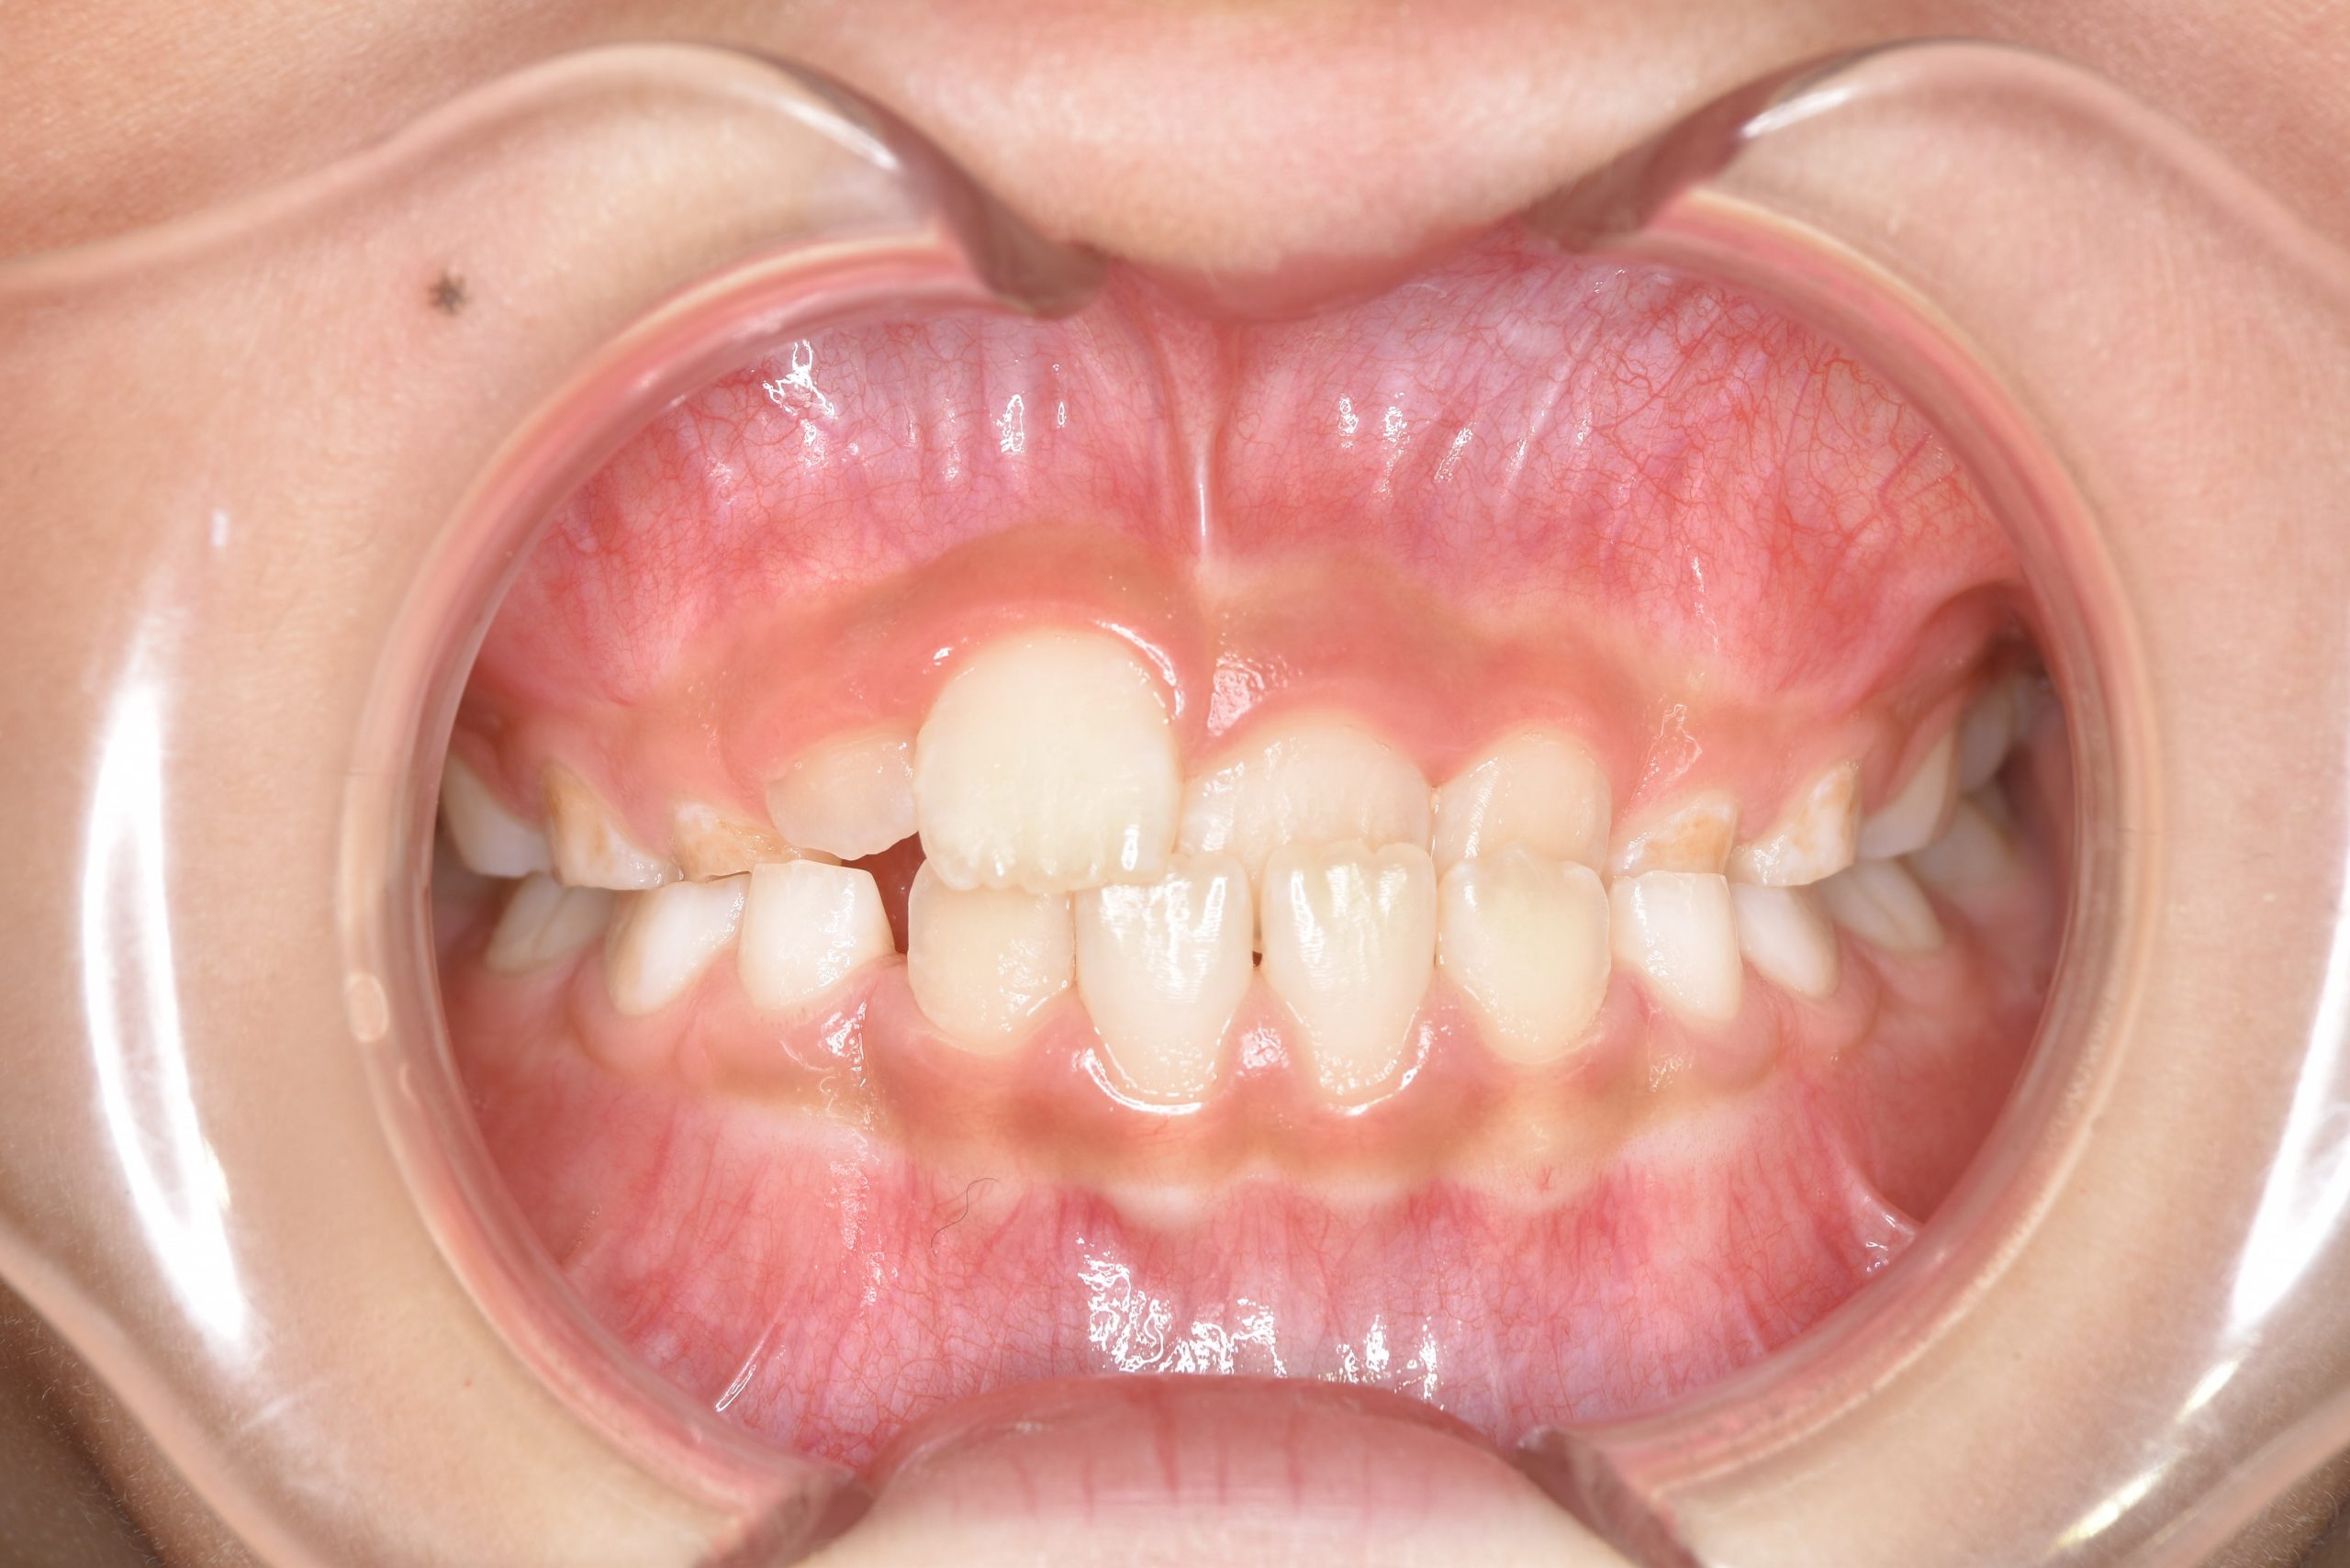

アフター

全顎ワイヤー矯正 症例_108

主訴 受け口|前歯がかみ合わない|顔貌

施術内容 小児矯正1期治療

治癒期間 3年11ヶ月間

費用 498,960円(税込)